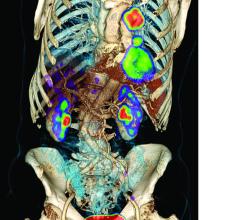

The last 12 months have seen significant growth in the positron emission tomography/computed tomography (PET/CT) segment of radiology, from both a manufacturing and a research perspective. One brand-new system received U.S. Food and Drug Administration (FDA) market clearance just months ago, while another started making its way into hospitals in the second half of last year. Several manufacturers also released software updates to help integrate PET/CT imaging into radiation therapy planning and execution. The increased interest was supported by several large studies exploring the advanced applications of PET/CT in oncology imaging.